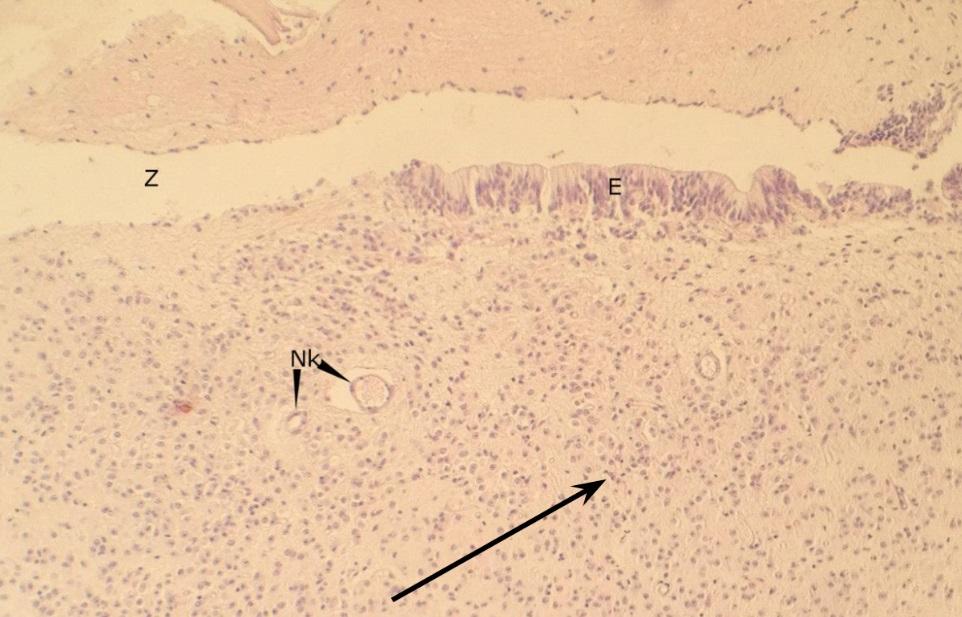

Pytanie 278

oskrzelik - mniejszy od oskrzela i bez tkanki chrzęstnej (płuco)

Pytanie 279

nabłonek wielorzędowy (płuco)

Pytanie 280

blaszka mięśniowa - błona Reissesena (płuco)